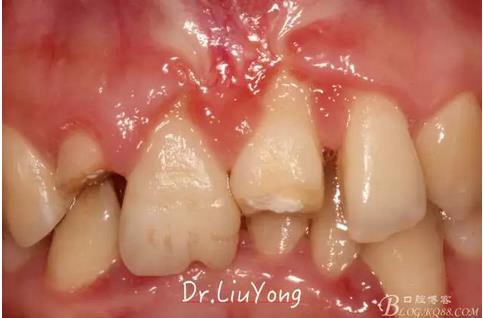

骨塊固定兩周后復(fù)查,如上圖

松動(dòng)牙固定一月后拆除,A1-B2無(wú)明顯動(dòng)度,但牙齦紅腫加重,給予全口齦上下潔治刮治術(shù),上藥,醫(yī)囑加強(qiáng)口腔衛(wèi)生,氯己定漱口液含漱。